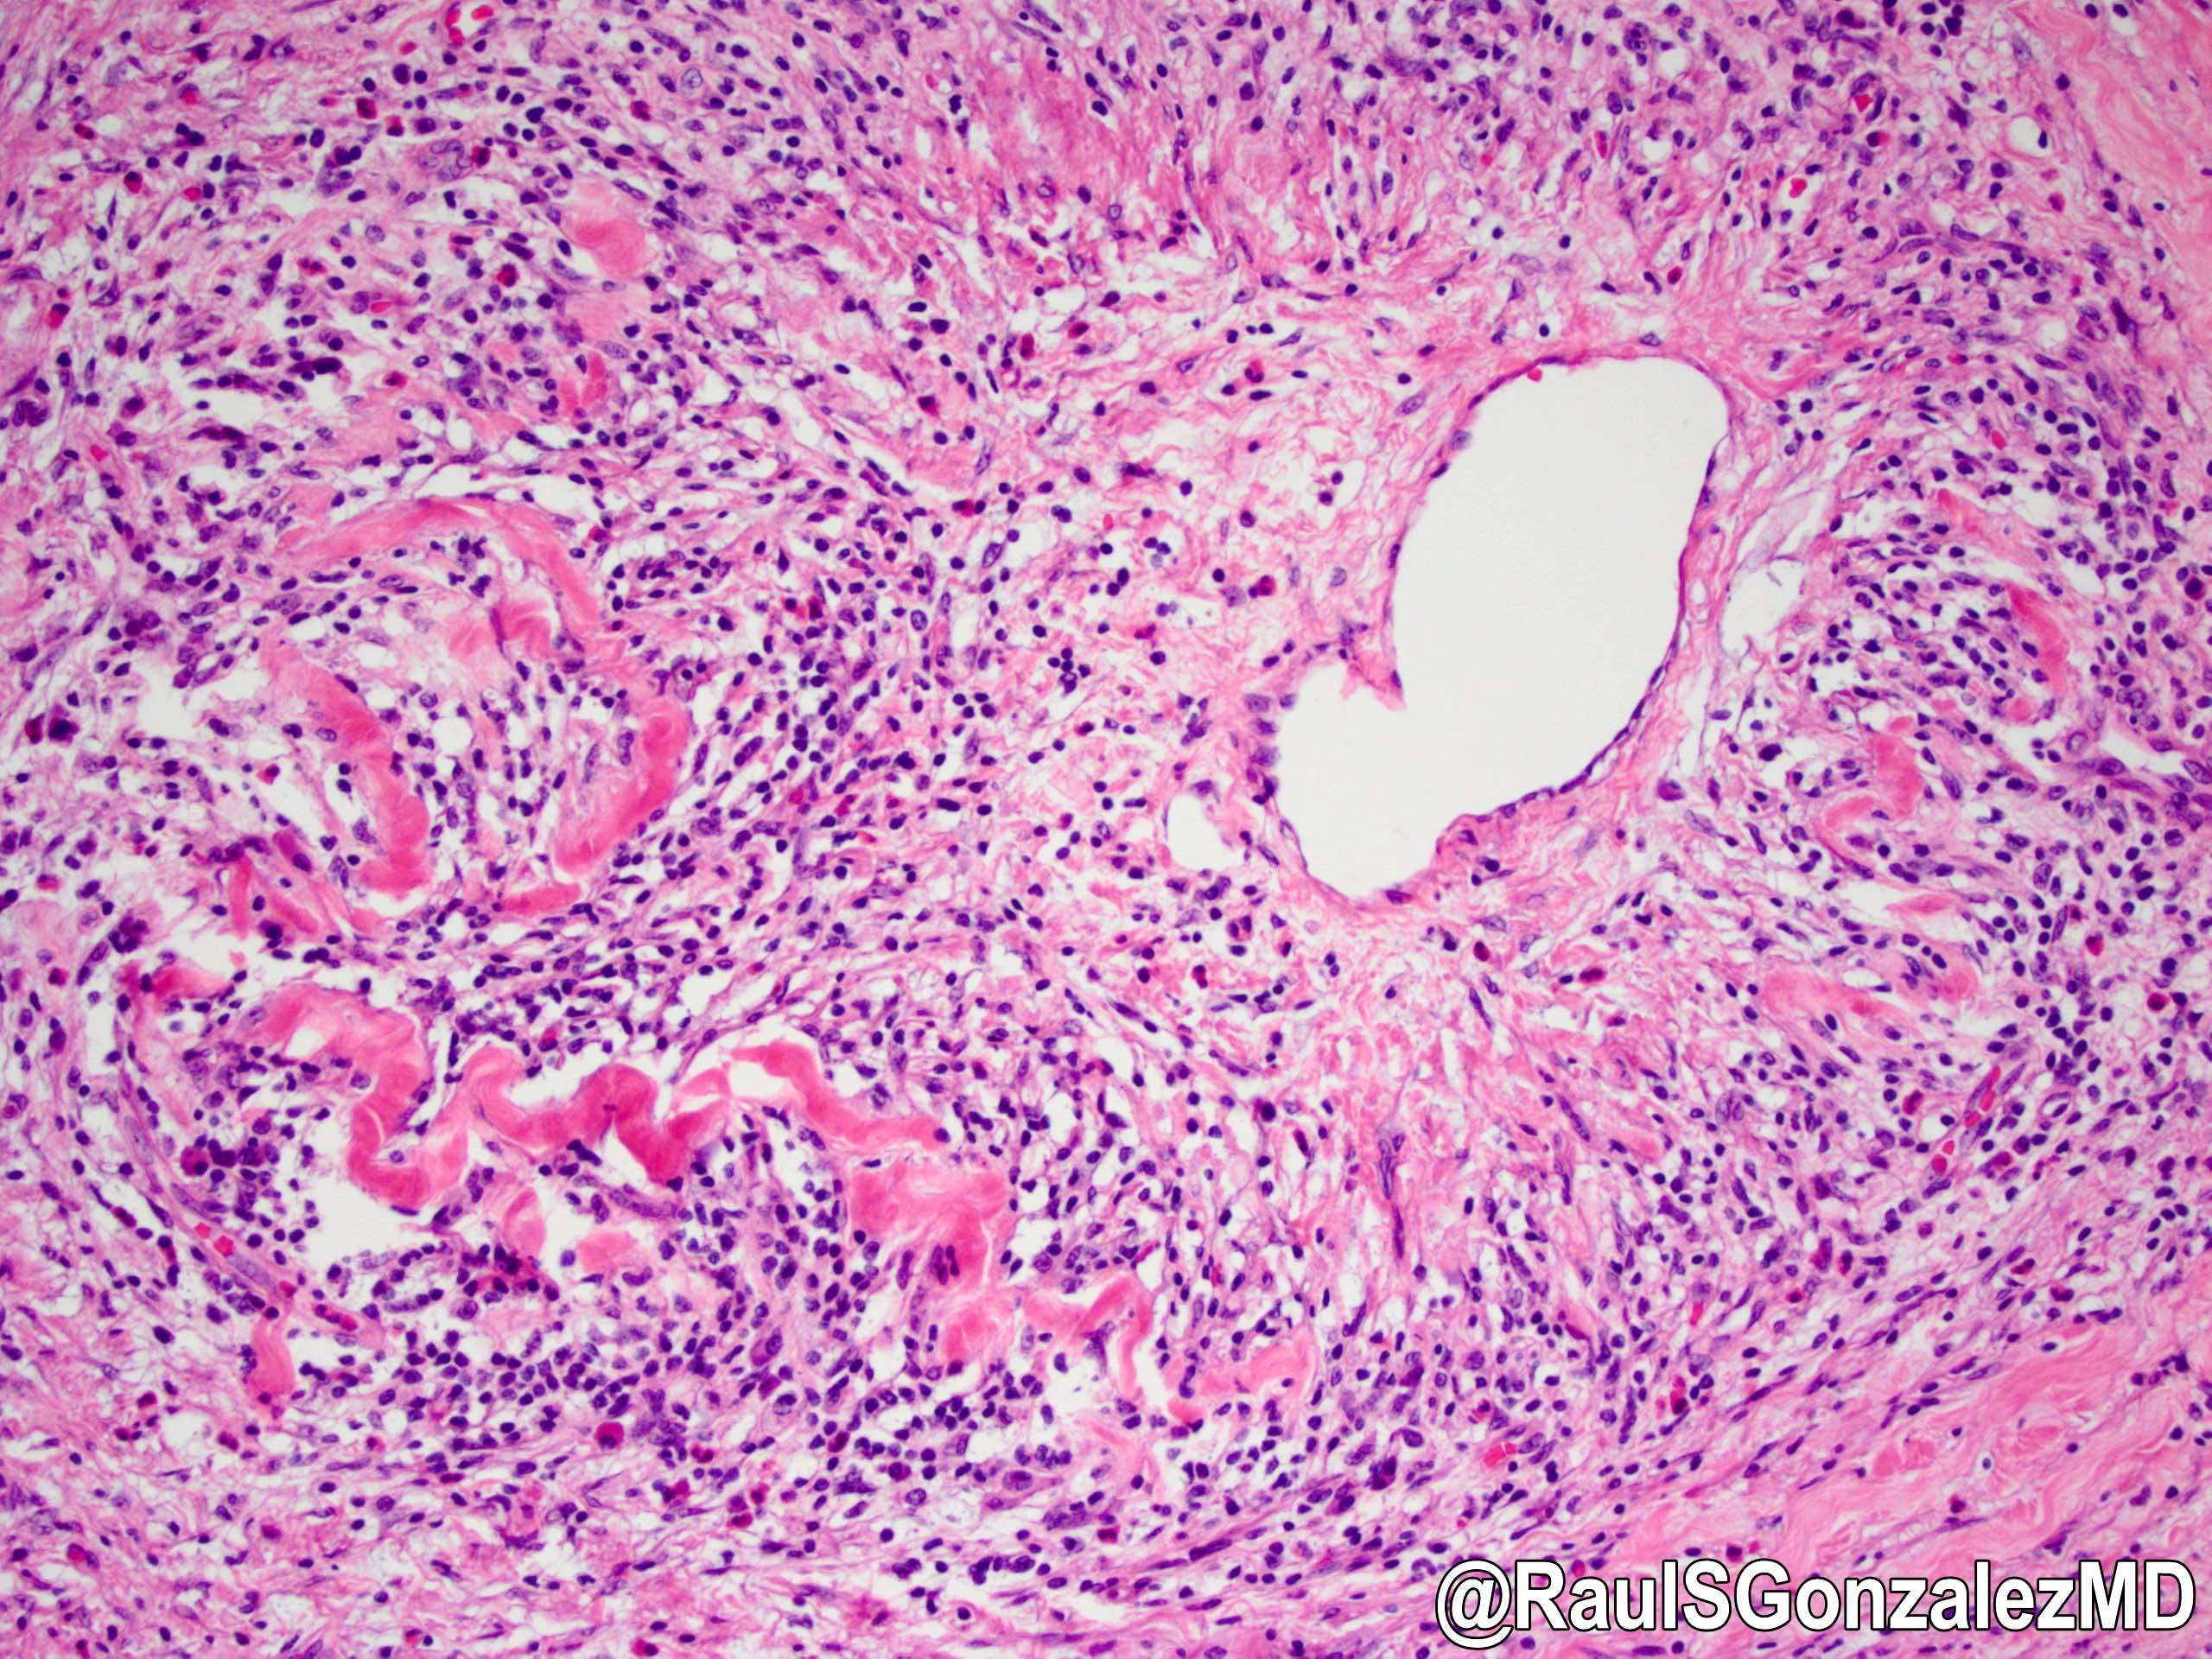

Microscopic (histologic) description

- Characteristic findings (at least 3 for level 1 criteria) (Pancreas 2011;40:352)

- Periductal lymphoplasmacytic infiltrate without granulocytic infiltration

- Obliterative phlebitis

- Storiform fibrosis

- Abundant (> 10 cells/high power field) IgG4 positive plasma cells

- Biopsy showing some but not all of the above features can be used as supportive evidence for the diagnosis of autoimmune pancreatitis (Pancreas 2011;40:352)

- Inflammation is localized within the pancreatic parenchyma and is centered around / within medium to large interlobular ducts, which causes shrinkage of the ductal lumen (Pathologica 2020;112:197)

- Inflammation can also be seen between the pancreatic parenchyma and peripancreatic adipose tissue (Pathologica 2020;112:197)

- Inflammation of the venous wall can progress to obliterative phlebitis with fibrosis of the lumen (Pathologica 2020;112:197)

- As the inflammation progresses, fibrosis becomes more diffuse, assuming a whorled or storiform pattern (Pathologica 2020;112:197)

- Perineural inflammation can also be present (Pathologica 2020;112:197)

Microscopic (histologic) images